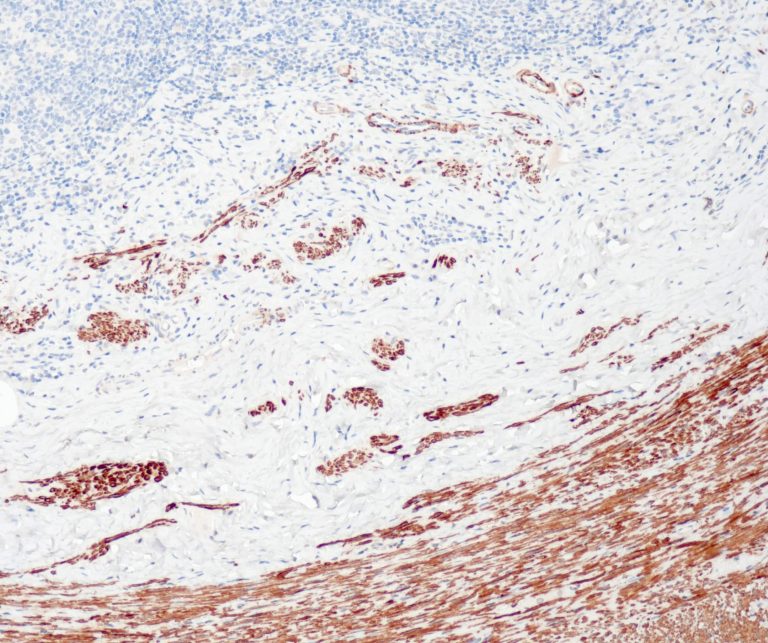

Vascular Pathology